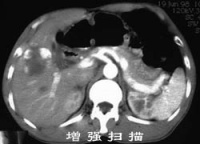

CT表现[编辑 | 编辑源代码]

在脑动静脉畸形未破裂出血前有较典型的CT表现。在平扫,可见

局灶性高低或低等混杂密度影,呈斑点、团块或条索状,边缘不清。其中高密度影为局灶胶质增生、血栓、钙化、新出血或畸形内缓慢血流和含铁血黄素沉着所致,低密度影则为小梗塞或陈旧出血,病灶周围有局限脑萎缩,没有明显占位效应,无周围脑水肿。部分病人平扫不能发现动静脉畸形,但注射造影剂,方能显示病灶。注射造影剂后,脑部动静脉畸形呈团块状强化,甚至可见迂曲血管影、供血动脉和引流静脉出血后的脑动静脉畸形则出现脑内血肿,蛛网膜下腔及脑室系统出血。根据出血时间长短表现高密度影、混杂密影及低密度影,血肿周围有低密度水肿区。同时有脑室受压变形及中线移位等占位效应。注射造影剂后,部分血肿边缘可出现畸形血管迂曲强化影,同时混杂密影血肿常有环状强化。

3、头部CT:平扫病变常为低密度、周围亦有低密度,若脑内出血可见高密度,

增强后血管区呈高密度,有时可见供血动脉和引流静脉。

2、头部CT可发现血肿及提供畸形血管的可能性。